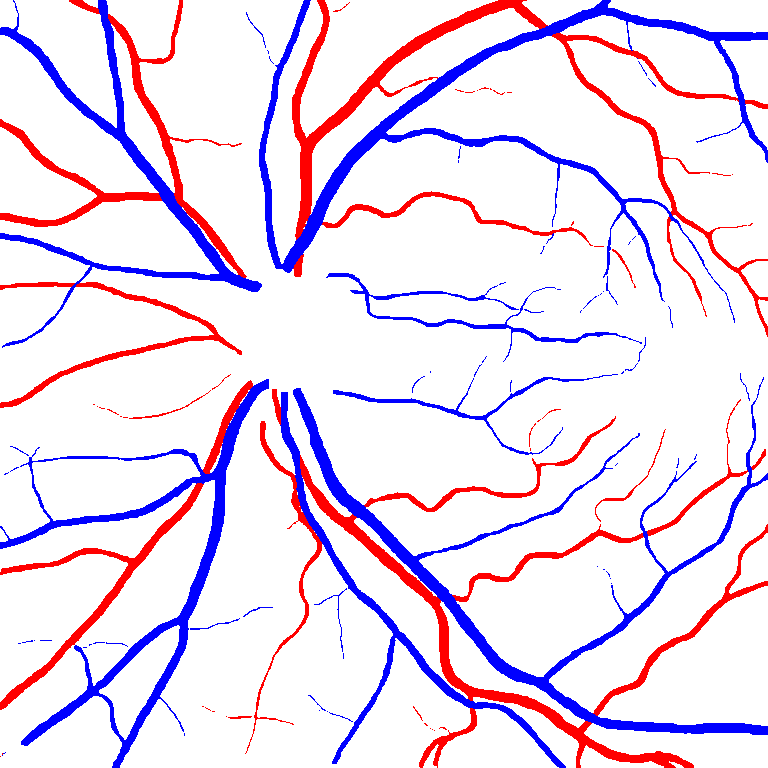

As reported in Table IV, we compared the SegRAVIR model against competing deep learning-based segmentation approaches on the RAVIR dataset. Evidently, SegRAVIR outperforms these methods as judged by all metrics for artery and vein classes with a healthy margin. In terms of Dice score, SegRAVIR outperforms CE-NET, IterNet and AG-Net by , and for artery segmentation and by , and for vein segmentation, respectively. Fig. 4 presents a qualitative comparison of the semantic segmentation outputs of SegRAVIR, CE-Net, and U-Net. Specifically, SegRAVIR yields more accurate vessel topology (i.e., thickness and orientation) segmentation with higher pixel-wise classification accuracy.

Table V presents quantitative performance benchmarks of SegRAVIR and other competing approaches for retinal artery and vein classification on the RITE dataset [11]. SegRAVIR outperforms previous state-of-the-art approaches in terms of accuracy, sensitivity, and specificity. Fig. 5 provides a qualitative comparison between segmentation outputs of SegRAVIR and the method of Hemelings et al. [40] on the RITE test set.